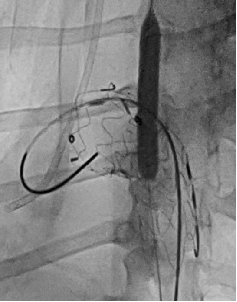

case 1

患者男性,51岁,主动脉夹层,通过Futhrough系统完成左锁骨下动脉(LSA)原位开窗重建。术中使用可调弯鞘(Fustar)和破膜系统,DSA显示破膜即刻成功,术后分支通畅,无并发症。

术前造影

穿刺破膜

球囊后扩

术后造影